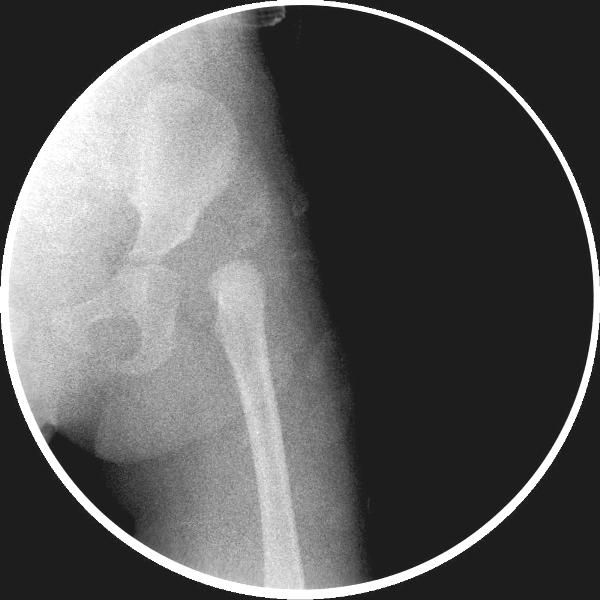

先天性左侧髋关节脱位。

左侧先天性髋关节脱位.

应该是典型的先髋。蛙式复位就可以了,何必ct呢。

左侧先天性髋关节脱位.典型!